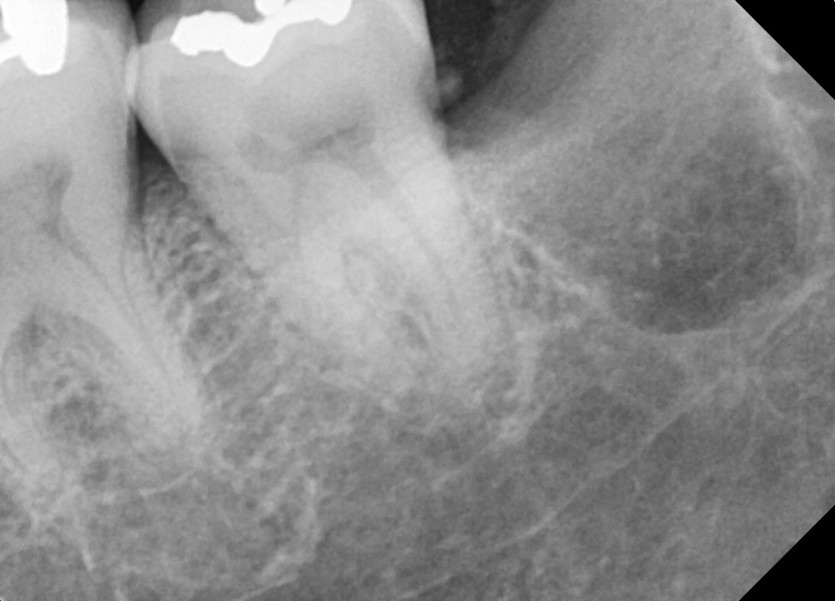

#28,38,48 사랑니 발치

구강 외과 전문의가 당일 발치했습니다.